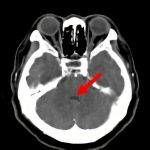

断層撮影

手術前2